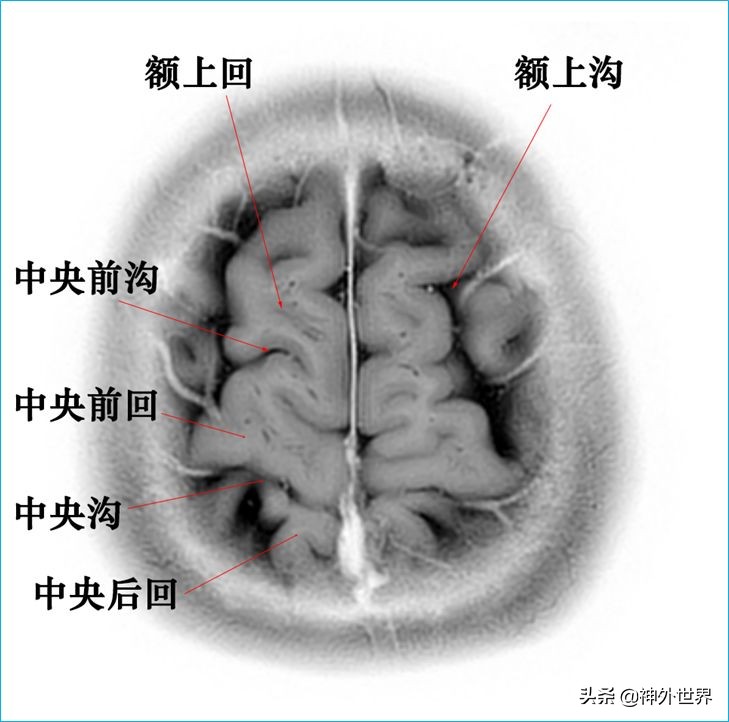

四、T2WI反相图学颅脑断层解剖

以下图片均来自我院3.0T核磁共振的T2WI反相图。标注均为我自己完成,水平有限,难免有误,还望各位老师多多指正。谢谢。